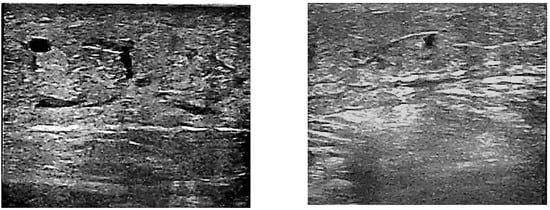

After the three-month treatment with diosmin, no changes were noted in the echo-Doppler assay; however, a reduction in the extravasation of edema fluid into the perivascular space was observed in 78% of patients from C3 and 83% of patients from C4 groups. This resulted in a decrease in edema, and the average leg circumference in the patients decreased from 30.74 (±0.58) cm to 29.11 (±0.39) cm in a significant manner (p < 0.05). Examples of perivascular space images before and after the diosmin treatment are shown in Figure 1a,b, respectively.

Figure 1.

Ultrasound images of the perivascular space in a patient before (a) and after (b) 3 months of diosmin treatment.